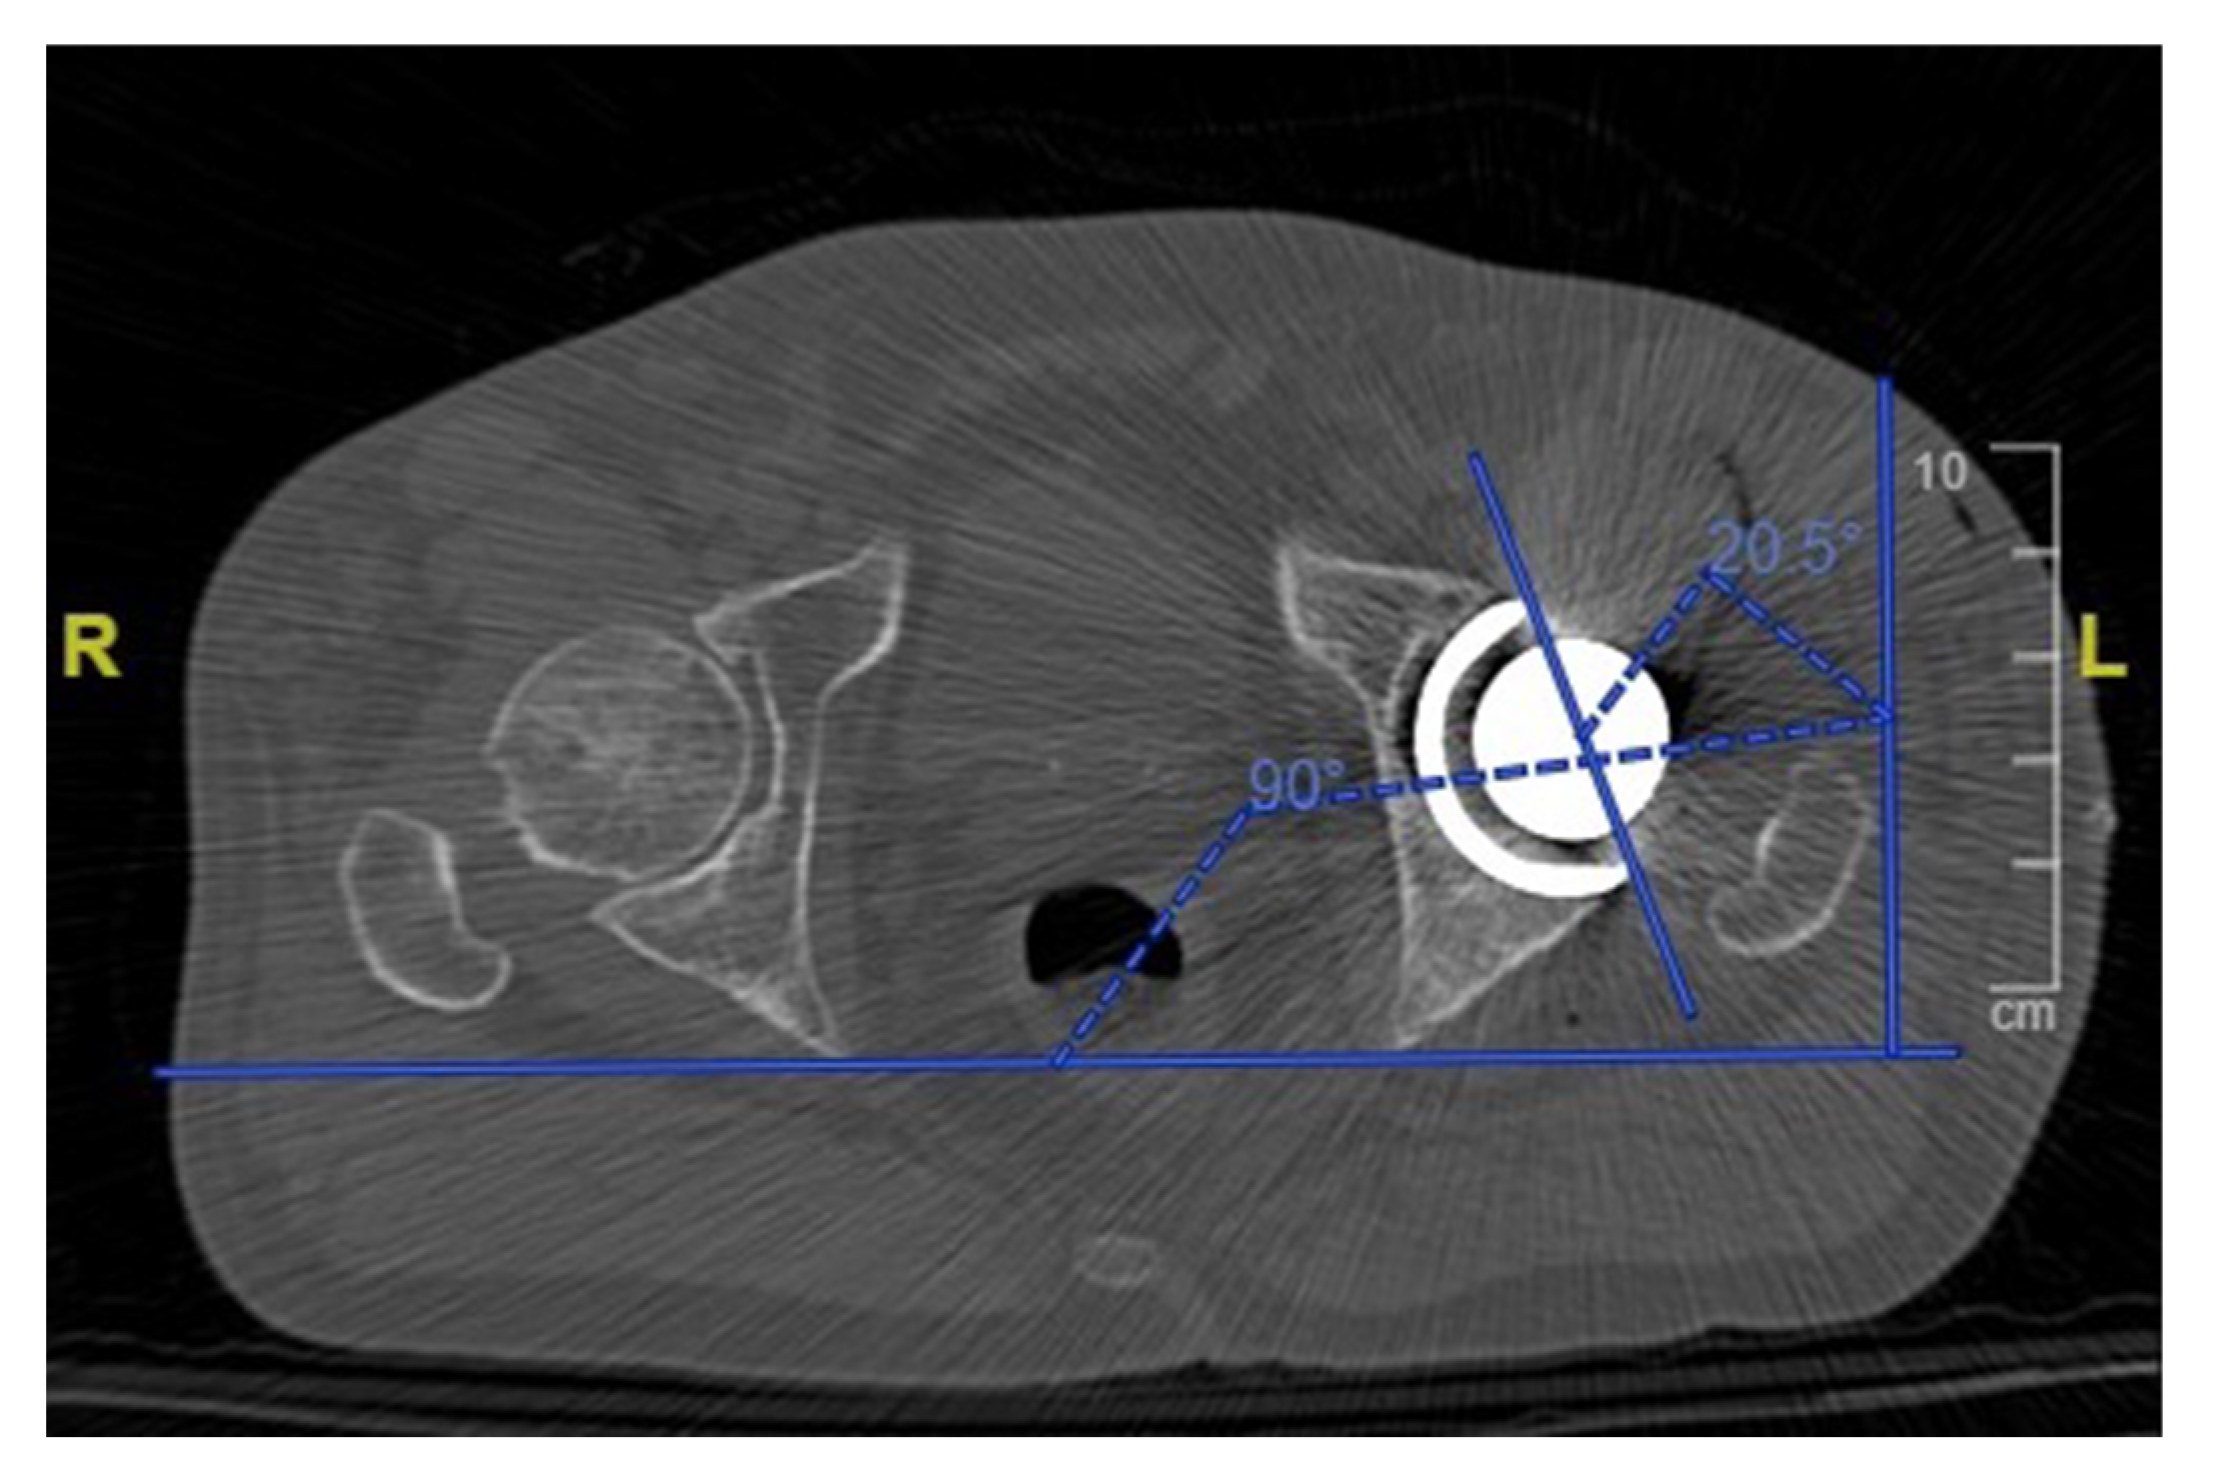

2.2. Postoperative CT Evaluation